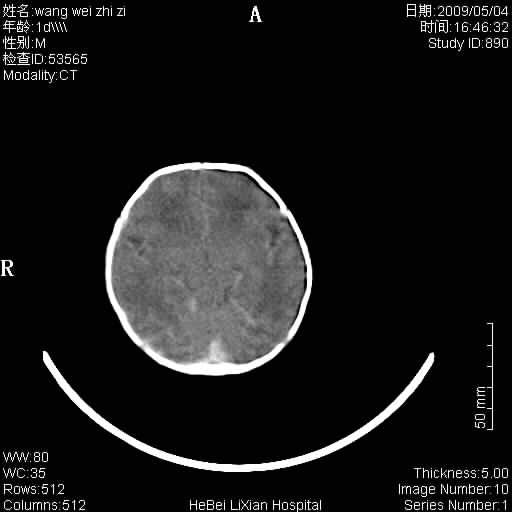

患者,男,1天,上肢抽动数次伴气促.有急产史.可以诊断珠网膜下腔出血吗?

局部5毫米薄层扫描

缺血缺氧性脑病,蛛网膜下腔出血。

此例符合缺血缺氧性脑病并蛛网膜下腔出血.